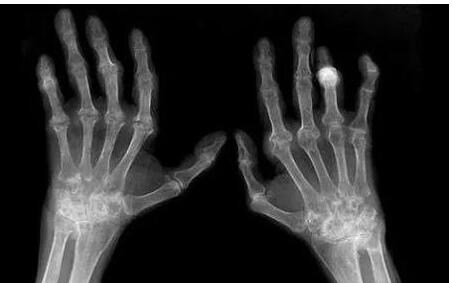

2、受累关节变成僵硬而畸形:

膝、肘、手指、腕部都固定在屈位,较后不能动弹都是类风湿性关节炎症状严重时的表现。